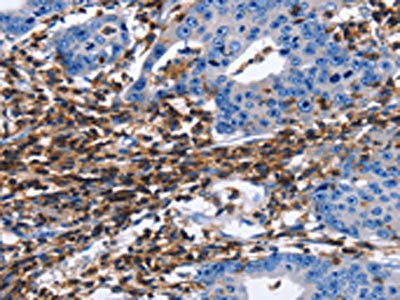

The image on the left is immunohistochemistry of paraffin-embedded Human gastric cancer tissue using CSB-PA480713(PTPRC Antibody) at dilution 1/40, on the right is treated with synthetic peptide. (Original magnification: ×200)